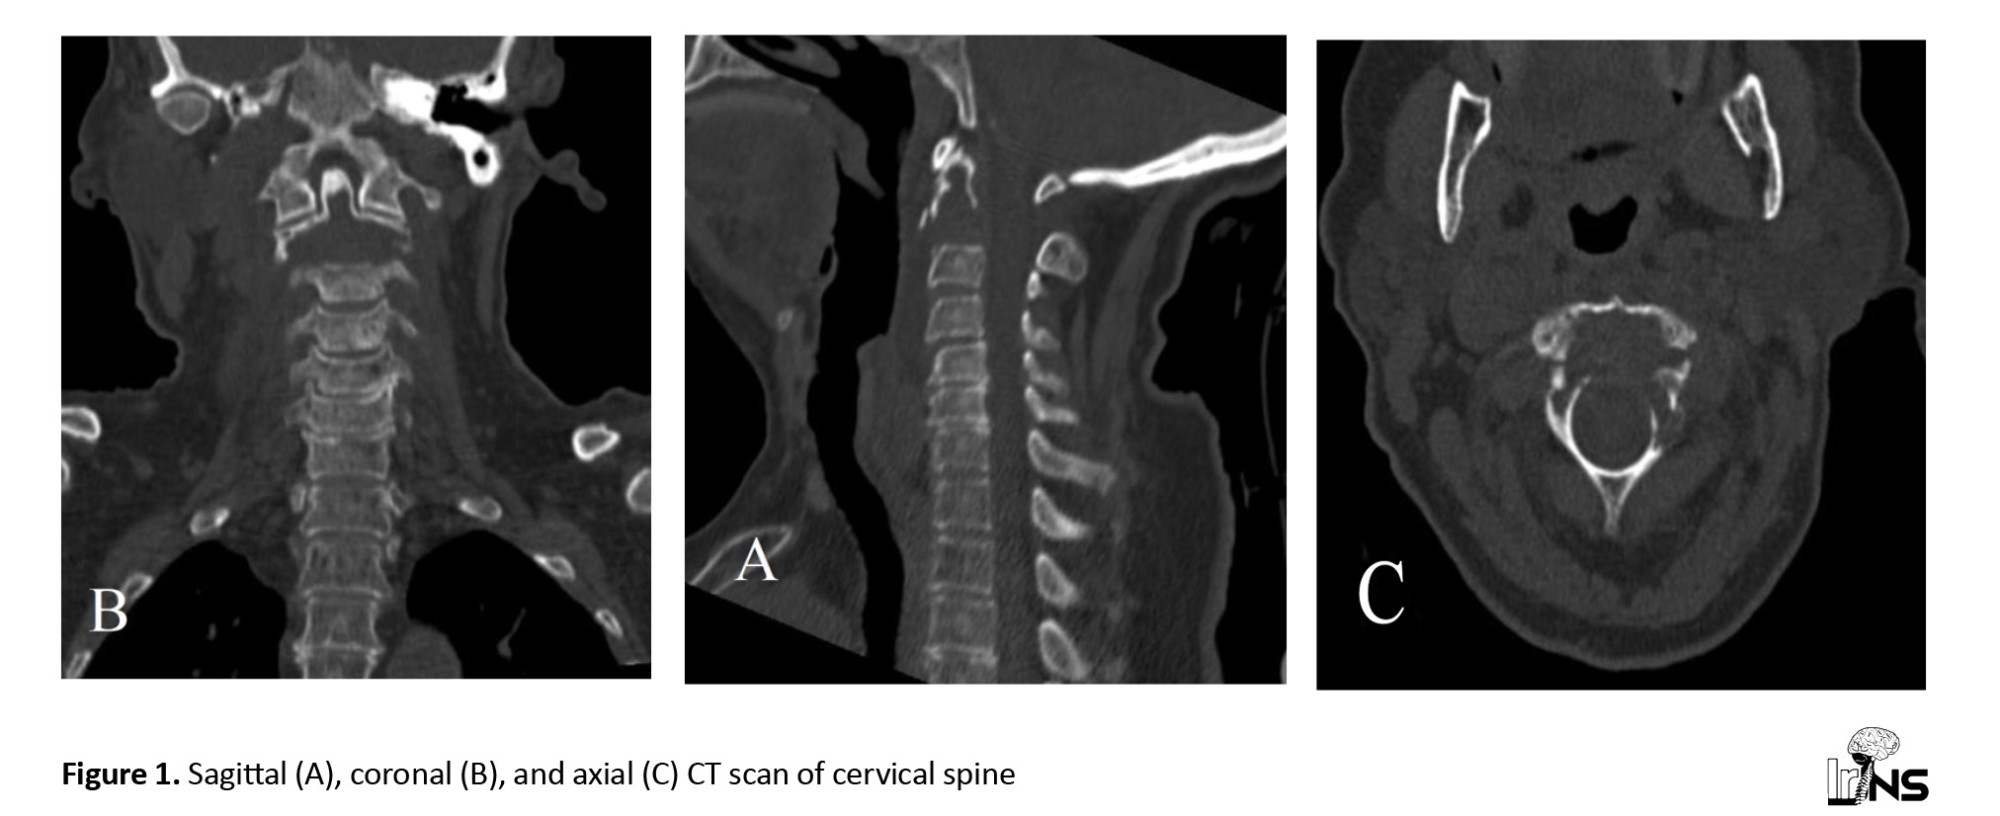

A 70-year-old woman presented with 6 months of progressive, severe axial mechanical cervical pain and “sensation” of skull instability. Primarily, she had complete concessions with intact upper and lower extremities without sensory or upper motor neuron symptoms. Computed tomography (CT) showed a lytic expansile lesion involving the body of C2 and left lamina but thinned anterior and posterior cortical borders with some disruption (

Figure 1).

Histological findings, including identifying monoclonal plasma cell infiltrates, are essential to establish a primary diagnosis. Our patient exhibited a lytic lesion on both MRI and CT, indicative of a malignant tumor. The CT showed expansive bone destruction, preserving the anterior and posterior borders. Patients presenting with tumor-induced pain may be good candidates for palliative therapies, such as radiation or bisphosphonate treatment, depending on the primary tumor type [12]. Our patient’s pain was mechanical and caused by craniocervical instability resulting from a pathologic fracture. After a comprehensive whole-body metastatic assessment, the primary tumor remained undiagnosed. Consequently, we opted for an invasive treatment approach as the patient was in good overall condition but symptomatic.